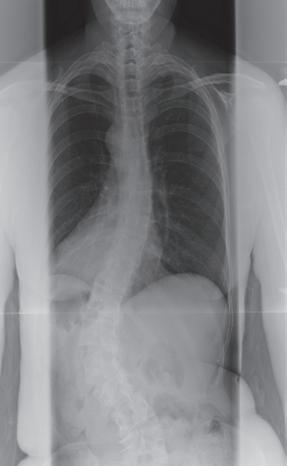

“My scoliosis wasn’t visible, so even though I didn’t look like I had a problem, I hurt.”

Nancy Swift - Dallas, Texas

Depressing. Painful. Exhausting. Just some of the words that people with scoliosis live with everyday. Scoliosis, which affects over 12 million people worldwide, can lead to progressive deformity in the spine as well as incapacitating pain. Too often people are told that there is nowhere else to turn … but there is.

The specialists at Baylor Scoliosis Center have performed over 600 spinal operations and developed pioneering techniques to help give you the one word you want to hear. Hope. For more information, call 1.800.4BAYLOR or visit www.TheBaylorScoliosisCenter.com.